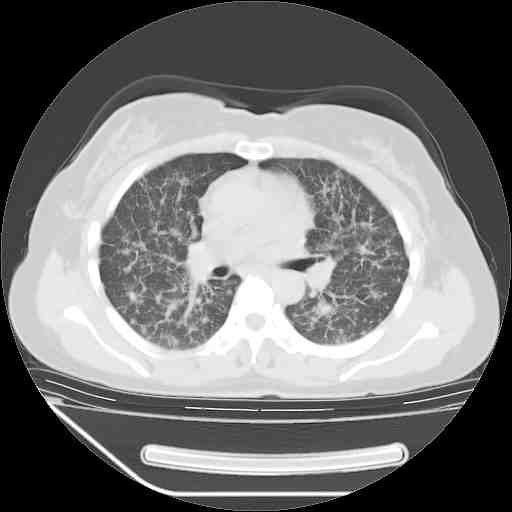

下面是今天刚刚做的,在上海治疗,吃了家属也说不清的一种药,一个月1万左右,

考虑  腺癌肺内转移,治疗较前病灶缩小、减少

支持肺癌并肺内淋巴管炎,  原发灶小了,但转移较前片明显了.

支持右肺下叶周围型肺癌并肺内淋巴管炎,  原发灶小了,但转移较前片明显了.。

标准的细支气管肺泡癌呀!治疗后病情有所控制,也没治愈的迹象!

支持右肺下叶周围型肺癌并肺内淋巴管炎;病灶有所控制。